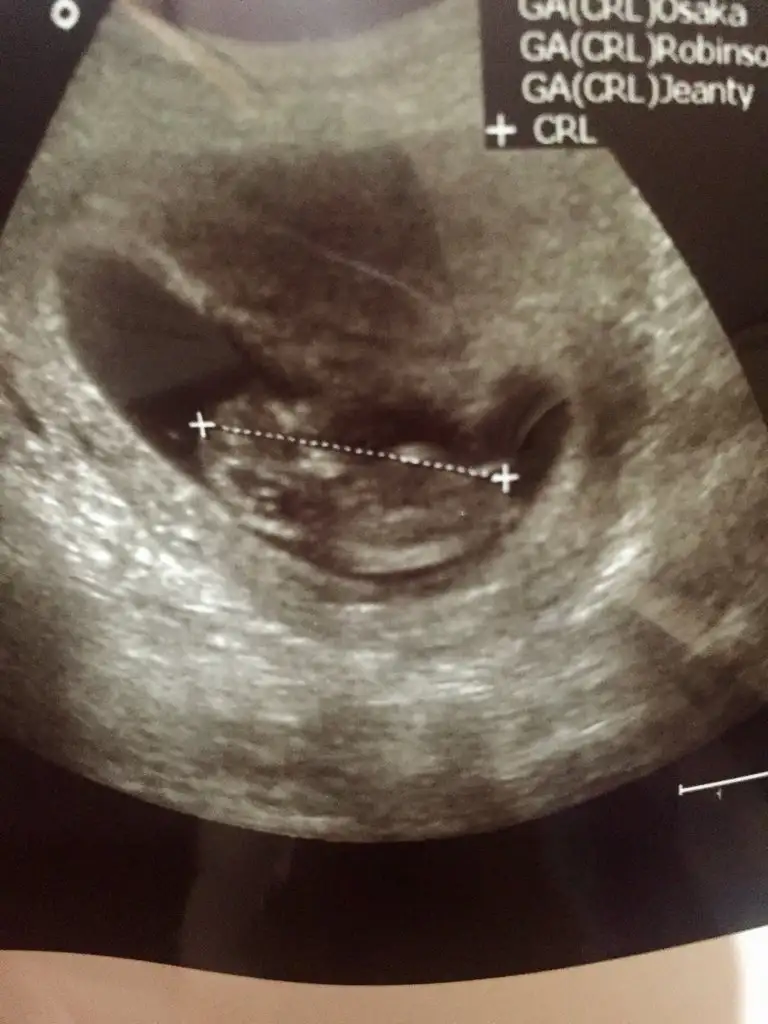

Erkek benceHanımlar benim çocuğuma da tahminlerinizi rica ederim meraklıyız biz biraz da(10+6 usg) Şimdiden çok teşekkür ederim

Kız gibiRica etsem bizi de tahmin eder misiniz? çok merak ediyorumburda 11+3 haftalığız